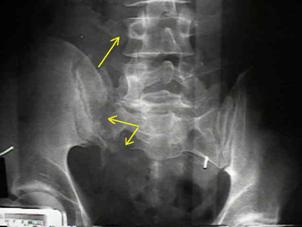

Banda de stabilizare Dallas Fractura de bazin. Radiografie in

incidenta AP

Inaintea

aplicarii benzii de stabilizare Dallas

Fractura de bazin

. Radiografie in incidenta AP Fractura de spina

iliaca antero-superioara

Dupa aplicarea benzii de stabilizare Dallas prin avulsie. - Stabila -